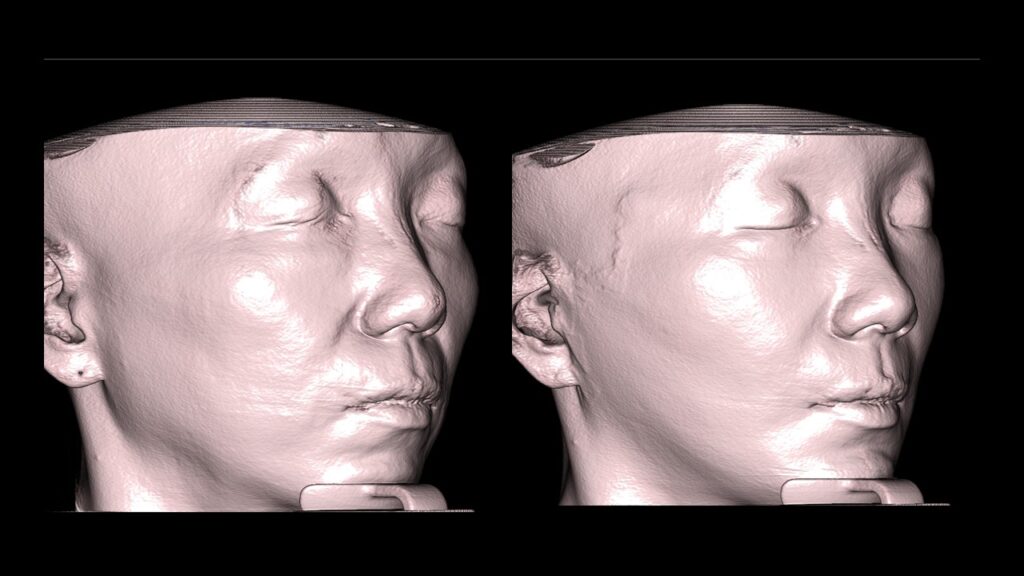

4. Case Studies (3DCT & Medical Photos)

Case 2: (Zygoma + Chin Advancement + Face Lift + Brow Lift) Dramatic improvement in the side profile and double chin within just 1 month.